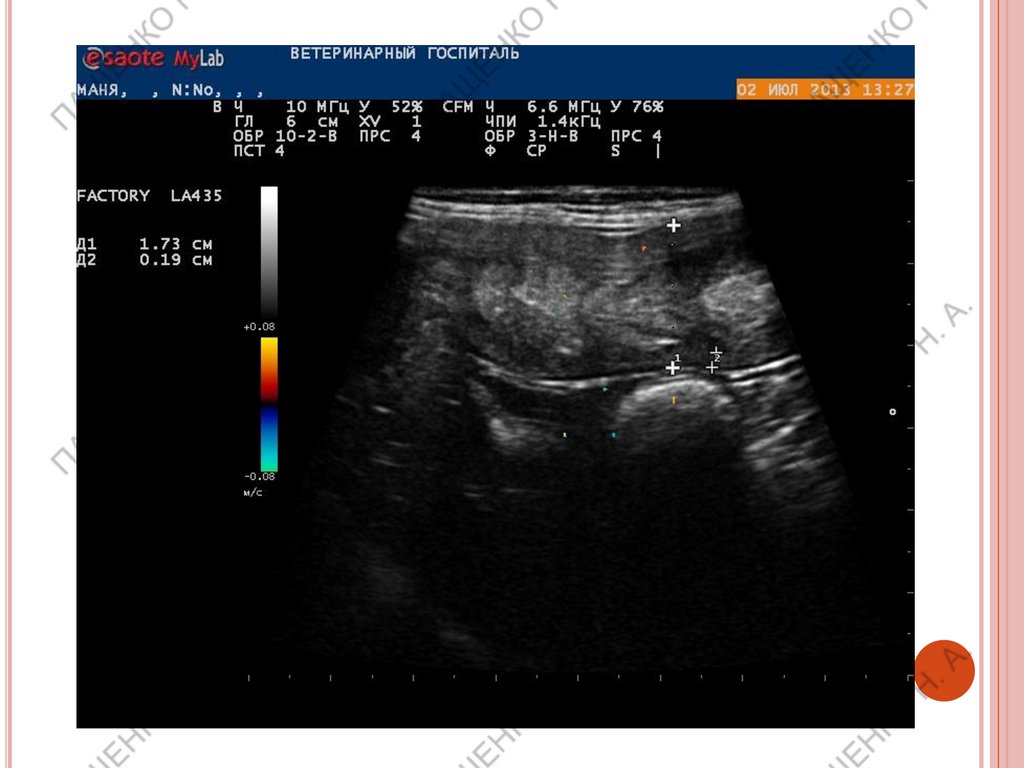

ЯИЧНИК В ЭСТРУС (ФОРМИРОВАНИЕ ФОЛЛИКУЛОВ)

В проэструс размер увеличивается, контуры становятся

бугристыми, появляются фолликулы с тонкими стенками,

размер зависит от породы, за сутки до овуляции размер

фолликулов от 0,5 до 1,1 см.

День овуляции – фолликулы уменьшаются в диаметре, контур

яичника может становится бугристым, но мб и гладким, можно

обнаружить солидные гипоэхогенные желтые тела. Вокруг

яичника может визуализироваться свободная жидкость.

Эструс – макс размер яичника на 5-6 день после овуляции,

контур бугристый. Желтые тела имеют анэхогенный центр, их

можно спутать с фолликулами, обычно толстостенные, мб до 5-9

мм в диаметре